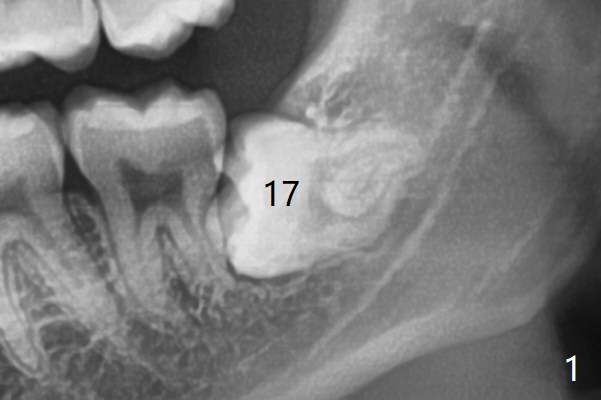

A 22-year-old man, asymptomatic, is going to have #1,16,17 and 32 extracted (Fig.1, fully bony impaction). For the large lower sockets (actually Buccal Impaction), collagen plug is placed in the inferior half, while Bone Cement (Bond Apatite from Augma (Fig.3 A)) and Osteogen plug (O) in the superior half at #32 and 17, respectively.